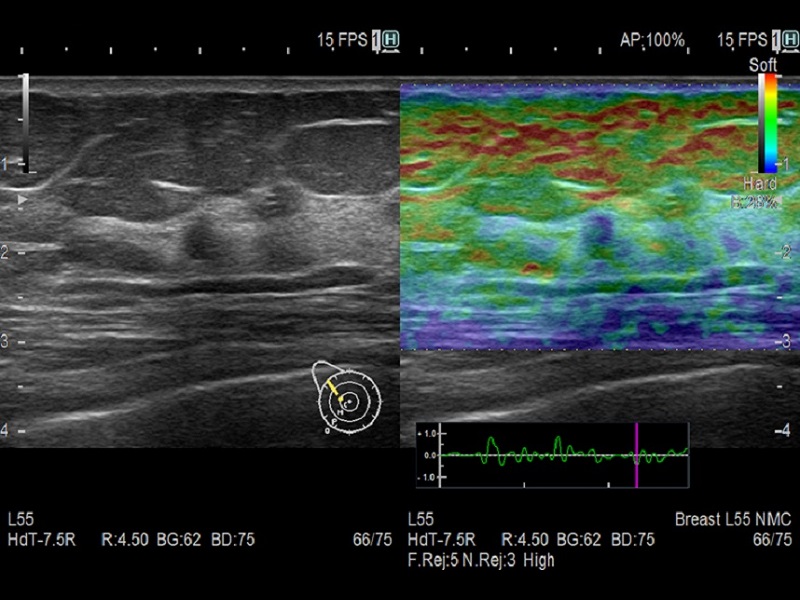

- Real-time Tissue Elastography(RTE)

- Assesses tissue strain in real time and differences in tissue stiffness as a color map – useful in a wide variety of clinical fields such as breast, thyroid gland and urinary structures.

- Estimates liver fibrosis staging in patients with hepatitis C (LF Index) with the abdominal convex transducer

- Supports time-saving automation features to improve objectivity, reproducibility and productivity

Dormed Hellas AR65 – Dual Gate Doppler Dormed Hellas AR65 – Breast RTE